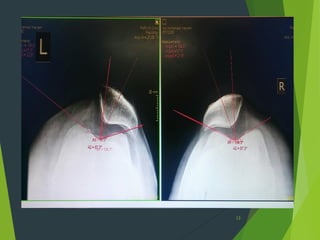

Lateral view

Crossing

sign

Insall-Salvati index:1.15

Right Left